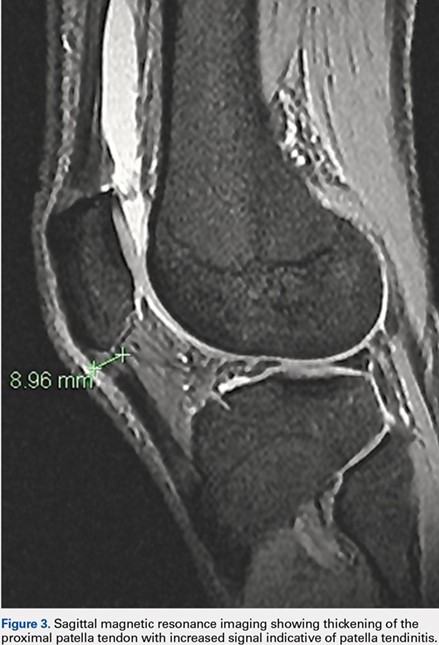

Four patients had free ossicles within the inferior patellar tendon consistent with unresolved Osgood-Schlatter’s disease (prevalence, 2.0%) (Figure 2). All 4 patients were male, which is consistent with the higher incidence of Osgood-Schlatter’s disease in males than in females. The average age of these patients was 27.5 years (range, 22-33 years).